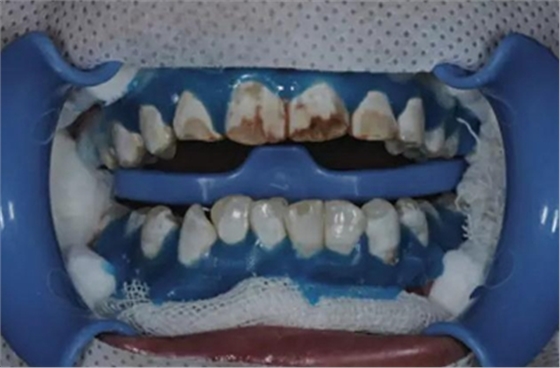

1、利用高速渦輪機(jī)配105 um金剛砂車針 (ML524, Diatech, Altstatten, Switzerland) 磨除200-400 um的牙釉質(zhì)。

2、利用中-細(xì)拋光盤 (Sof-Lex, 3M ESPE, St Paul, MN, USA) 打磨釉質(zhì)表面并消除尖銳角。

3、在牙頸部涂布光固化的牙齦保護(hù)劑 (Beyond Technology Inc, Santa Clara, CA, USA),在釉質(zhì)表面涂布含硅脲微粒和6.6%鹽酸的研磨膏 (Opalustre, Ultradent Products, South Jordan, UT, USA),利用橡皮杯 (Oralcups, Ultradent Products) 微打磨120 s。

4、微打磨后,利用診室內(nèi)漂白劑 (Opalescence Boost, 38%H2O2 Ultradent Products) 減輕氟斑牙表面的棕色著色。

隨后,在牙面上涂布抗敏感保護(hù)劑(Fluorinated protector, Beyond Technology Inc),停留5 min后吸除,水徹底沖洗牙釉質(zhì)表面并移除牙齦保護(hù)劑。

在診室內(nèi)漂白的同時(shí)聯(lián)合運(yùn)用家庭漂白。在使用8支10%過氧化脲凝膠 (Ultradent Products) 后,患者很滿意漂白效果。

5、由于氟斑牙存在釉質(zhì)礦化不全等問題,家庭漂白兩周后,使用標(biāo)準(zhǔn)的樹脂滲透技術(shù) (Icon, DMG Products, Hamburg. Germany) 來預(yù)防釉質(zhì)齲。最后,徹底改變患者的前牙美學(xué),并在一年后仍保持穩(wěn)定。